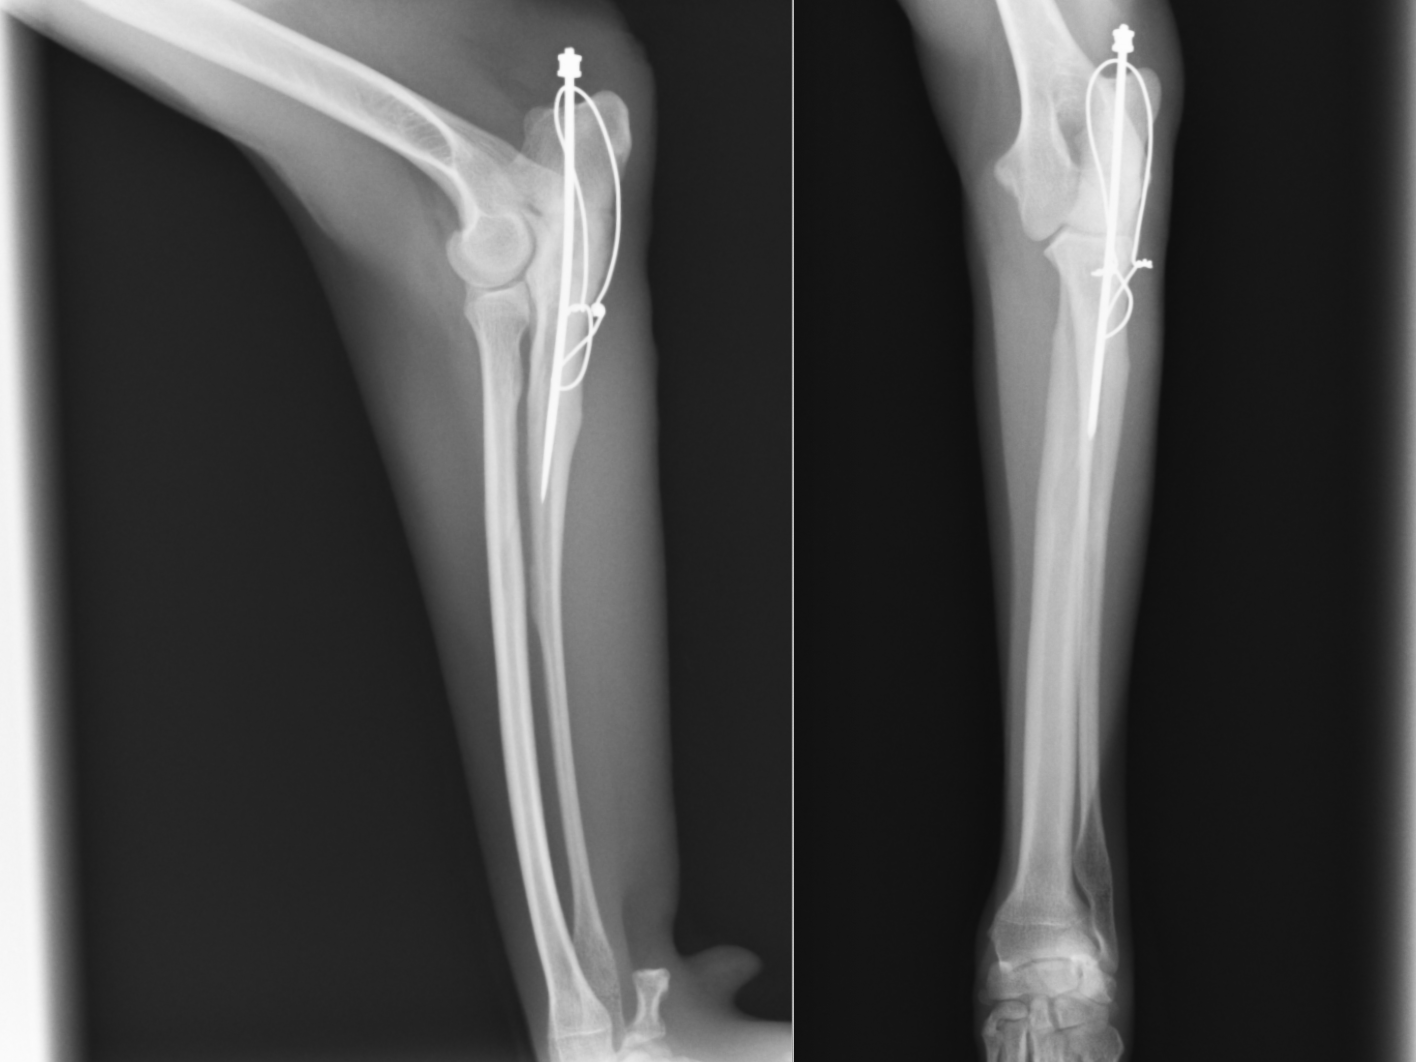

2ヶ月後には骨折線がかなり見えにくくなり骨の癒合が進んでいます。そのため抜ピンを行いました。

ピンを抜いたところです。ほぼほぼ正常な骨形態に戻っているのがわかるかと思います。